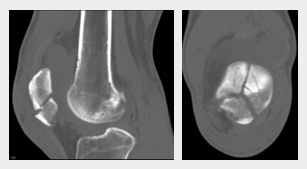

Wenn das Röntgenbild nicht ausreicht bzw. der Bruch auf dem Röntgenbild nicht sichtbar ist, wird noch ein CT gemacht, selten noch ein MRT (1'22''). Dann sieht man die Details. Der Bruch der Kniescheibe kann sein

-- ein Teilabriss

-- ein Querbruch

-- ein Längsbruch (1'32'') [web03].

Diverse Brüche der Kniescheibe,

Sammelfoto: Abrissfraktur, Querfraktur, Längsfraktur,

Sternfraktur

Diverse Brüche der Kniescheibe, Sammelfoto: Abrissfraktur, Querfraktur, Längsfraktur, Sternfraktur [7]

Bruch der Kniescheibe als

Sternbruch, Röntgenfotos

Bruch der Kniescheibe als Sternbruch, Röntgenfoto [8]

[8] Gebrochene Kniescheibe: Sternbruch, 2 Röntgenfotos: https://www.ctisus.com/teachingfiles/musculoskeletal/259391